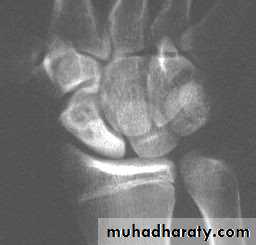

The patient presents with a wrist injury, but there is no dinner-fork deformity. Instead, there is a ‘garden spade’ deformity.X-ray

There is a fracture through the distal radial metaphysis; a lateral view shows that the distalfragment is displaced and tilted anteriorly – the

opposite of a Colles’ fracture.